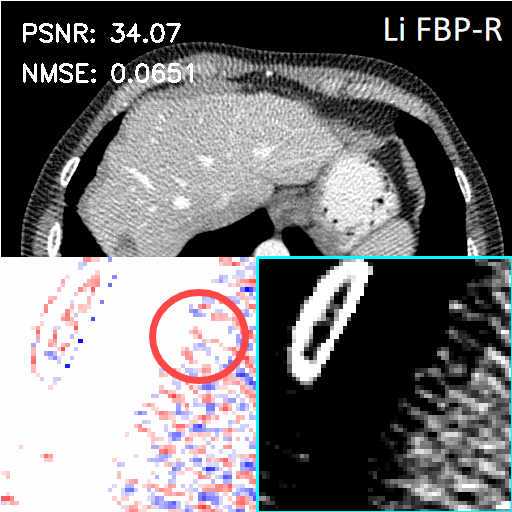

4.3 Results on more sparse-view cases

To assess the robustness of the proposed LInFBP, the data at 360 views, 145 views, 100 views, 72 views and 36 views are utilized. Fig. 6 shows the CT images reconstructed by Li FBP-R, Li FBP-H, F-LInFBP and L-LInFBP methods at 100 views. It can be seen that the proposed F-LInFBP and L-LInFBP can properly learn the continuous backprojection representation, leading to the effective recovery of some fine structures compared to the direct FBP-reconstructed CT images. Furthermore, Table 3 presents a comparison of evaluation metrics among the FBP, F-LInFBP, and L-LInFBP methods based on tests with three different sampling views. As the number of sampling views increases, the quantitative assessments of all competing methods achieve gradual improvements in reconstruction performance. Notably, both the proposed F-LInFBP and L-LInFBP methods outperform the traditional FBP algorithm. And interestingly, despite its simpler basis function constructions, the proposed L-LInFBP demonstrates the potential to achieve comparable or even better reconstruction performances compared to the proposed F-LInFBP with more complex Fourier basis functions, as also illustrated in Fig. 6.